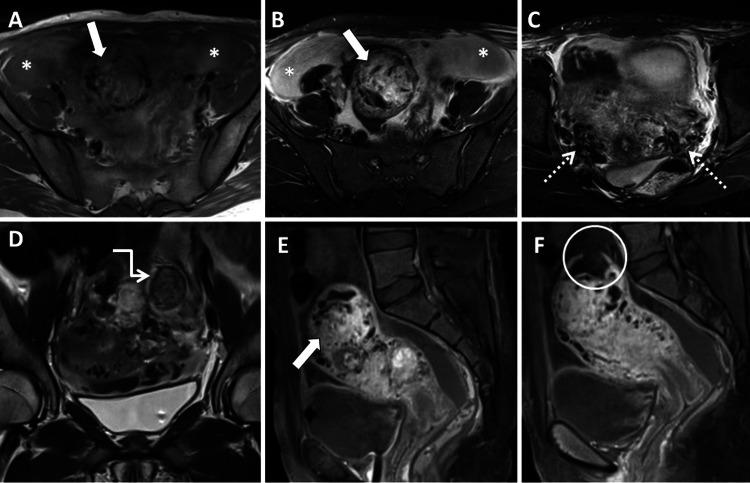

Choriocarcinoma, an aggressive gestational trophoblastic disease, infrequently manifests with spontaneous uterine perforation. We report the case of a 22-year-old female with five months of amenorrhea presenting with acute abdominal pain. Ultrasound and MRI assessment highlighted a uterine perforation with choriocarcinoma. Subsequent total abdominal hysterectomy revealed choriocarcinoma in the bicornuate uterus with uterine perforation. Histopathological analysis confirmed the diagnosis of choriocarcinoma in the cornu of the uterus. Timely diagnosis is vital to reduce mortality. Notably, choriocarcinoma in a bicornuate uterus is exceptionally rare. Radiological evaluations are critical for diagnosis, staging, and follow-up.

绒毛膜癌是一种侵袭性妊娠滋养细胞疾病,很少表现为自发性子宫穿孔。我们报告一例22岁女性,停经5个月,出现急性腹痛。超声和磁共振成像评估显示子宫穿孔合并绒毛膜癌。随后的全腹子宫切除术显示双角子宫绒毛膜癌伴子宫穿孔。组织病理学分析证实子宫角部为绒毛膜癌。及时诊断对于降低死亡率至关重要。值得注意的是,双角子宫绒毛膜癌极为罕见。影像学评估对诊断、分期及随访至关重要。